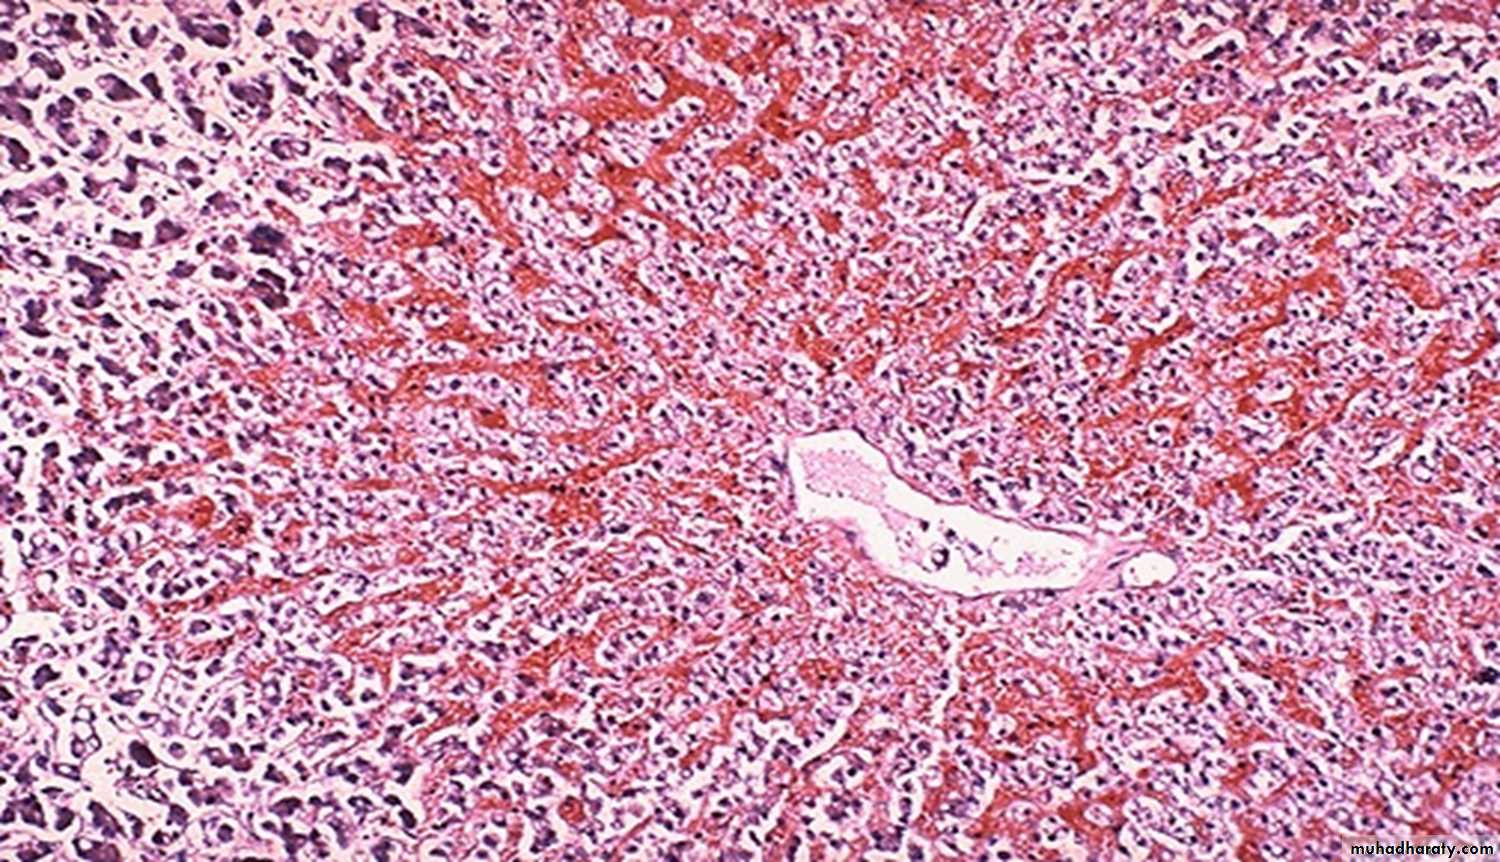

60 years male with "right sided" heart failure. (liver)

Description and diagnosischronic passive congestion of the liver. dark red congested regions that represent accumulation of RBC's in centrilobular regions.